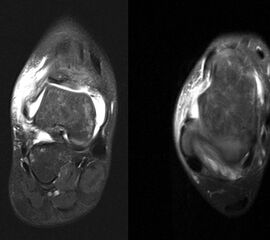

Schnittbildverfahren sind immer dann indiziert, wenn der Verdacht auf Begleitverletzungen besteht, das Schmerzniveau inadäquat hoch ist, oder die akuten Beschwerden innerhalb einer Woche nicht weitgehend abgeklungen sind 31 (Abb. 4-6).